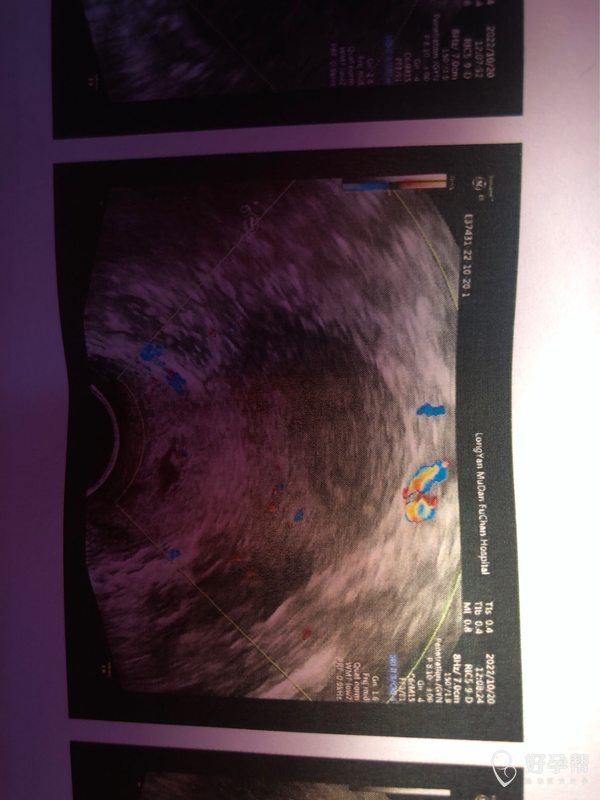

医生好这是我月经第8天的阴道彩超图请问按图上

可以继续观察子宫内膜厚度、形态、血流等。月经第8天,时间短,建议继续监测子宫情况。

现在已经月经第几天了,监测排卵需要动态观察。